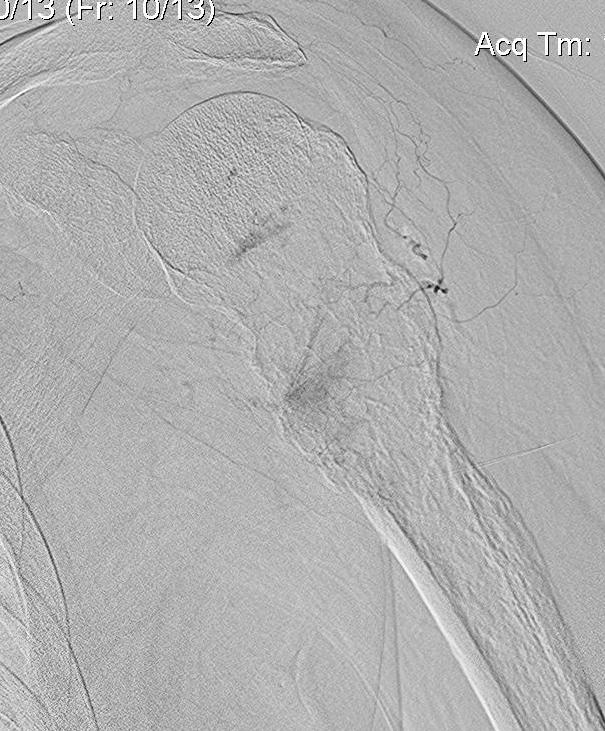

Pre-operative Arterial Embolization

Indications

- renal cell carcinoma

- thyroid carcinoma

Results

- embolisation of RCC metastasis in 107 patients

- success in 96%

- all patients had variable ischemic pain for 2 - 4 day

- 41 cases with embolization prior to surgery compared to 41 cases without

- embolization reduced blood loss, transfusion, and surgical times